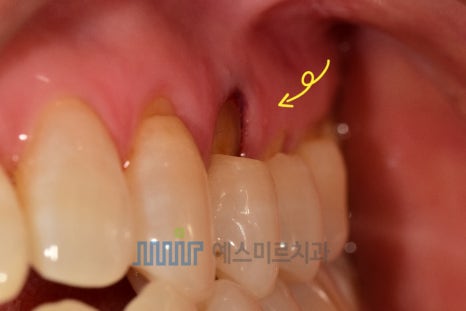

๊ฒ์ง ๊ฒฐ๊ณผ, ์น๋ ํ๊ณผ ์ค๋๋ ๋ง๋ชจ๋ก ์ธํ ์น๊ฒฝ๋ถ ๋ง๋ชจ์ฆ์ด ํ์ธ๋์๊ณ ,

๊ทธ์ค ํ ์น์๋ ์๋ชธ ๊ฒฝ๊ณ๊น์ง ๊น๊ฒ ํ์ธ ์ํ์์ต๋๋ค

๐ ๏ธ ์น๋ฃ ๊ณผ์

์์ค๋ฏธ๋ฅด์น๊ณผ์์๋

GC์ฌ์ '๋กํ๋ก(Lo Flo)'์ '๋ณธ๋ํ'์ ์ฌ์ฉํด ๋ ์ง ์ถฉ์ ์ ์งํํ๊ณ ์์ต๋๋ค

๐ ๋ณธ๋ํ ๋ ์ง

๋ณธ๋ํ์ ์น์์ ์ ๋ถ์ด์๊ณ ,

์ ์ง๋ ฅ๋ ์ข์ ํธ์

๋๋ค

์น๊ฒฝ๋ถ ๋ง๋ชจ ๊ฐ์ ์๋ฏผํ ๋ถ์ ์น๋ฃ์ ์ ํฉํฉ๋๋ค.

์์์ด ๋ค์ํด ํ์์ ์น์์๊ณผ ์์ฐ์ค๋ฝ๊ฒ ์กฐํ๋ฅผ ์ด๋ฃจ๋ฉฐ,

์ฌ๋ฏธ์ฑ๋ ๋ฐ์ด๋ฉ๋๋ค.

โป ์ฐธ๊ณ ๋ก, ์น๊ฒฝ๋ถ ๋ง๋ชจ ์น๋ฃ์๋ ๋ ์ง ์ธ์๋ 'GI'๋ผ๋ ์ฌ๋ฃ๋ฅผ ์ฌ์ฉํ๋ ๊ฒฝ์ฐ๊ฐ ์์ง๋ง,

์ค๋ ์๊ฐํ๋ ์ผ์ด์ค๋ ์ ์ง๋ ฅ์ด ์ข์ ๋ณธ๋ํ ๋ ์ง์ ์ด์ฉํ ์น๋ฃ๋ฅผ ํ์ต๋๋ค ๐

์น๋ฃ ํ ํ์๋ถ์ ์๋ฆผ ์ฆ์์ด ์ค์ด๋ค์๊ณ ,

๋์ผ๋ก ๋ณด๊ธฐ์๋ ๋งค๋๋ฝ๊ณ ์์ฐ์ค๋ฝ๊ฒ ํ๋ณต๋ ์น์ ํํ์ ๋ง์กฑํดํ์

จ์ด์!